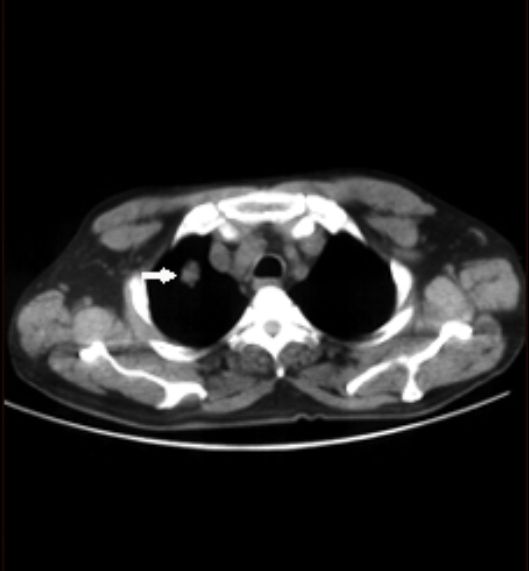

이 검사는 X선을 여러 각도에서 투사해 가슴 속을 단면으로 나누고, 컴퓨터가 이를 조합해 입체적으로 보여줍니다. 흉부ct로 볼수있는 질환 폐, 기관지, 심장, 혈관, 흉막, 림프절, 늑골까지 모두 관찰할 수 있어요. 몸을 절개하지 않고 내부를 볼 수 있으니 환자에게 부담이 적습니다. 조영제(혈관이나 염증 부위를 선명하게 보여주는 약물)를 사용하는 경우에는 정맥으로 주입하기도 하지만, 대부분은 통증이 거의 없습니다.

흉부ct로 볼수있는 질환 폐질환뿐 아니라 심장과 혈관, 흉막, 림프절, 뼈 구조까지 한 번에 보여줍니다. 폐렴, 결핵, 폐기종, 기관지확장증, 간질성 폐질환 같은 호흡기 질환은 기본이고, 폐에 생긴 작은 결절이나 혹도 세밀하게 확인할 수 있습니다. 폐암이나 전이암처럼 초기에 증상이 거의 없는 병은 CT로 발견되는 경우가 많아요.

혈관 관련 질환으로는 폐색전증(혈전이 폐혈관을 막는 병)이나 대동맥 박리(혈관 벽이 찢어지는 상태), 흉부 대동맥류(혈관이 부풀어 터질 위험이 있는 질환) 등이 있습니다. 조영제를 주입하면 혈관 내부 흐름까지 볼 수 있죠.

흉부CT는 병이 있는지 없는지를 넘어서, 병의 진행 정도와 주변 장기 침범 여부까지 보여줍니다. 예를 들어 폐암의 경우, 5mm 미만의 아주 작은 결절까지 찾아내고, 종양이 혈관이나 기관지에 닿았는지도 확인합니다. 초기에 잡아내면 완치율이 크게 높아지죠.